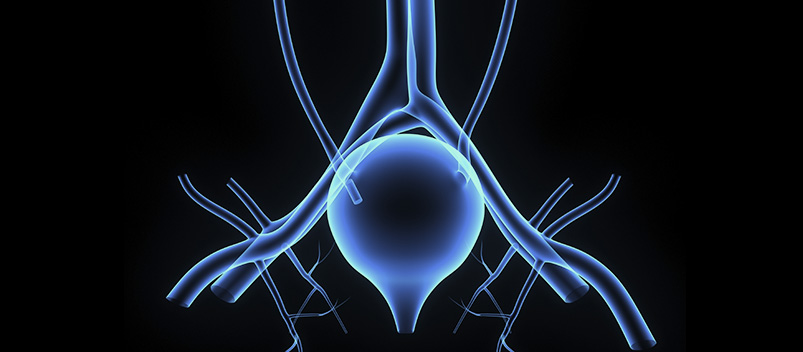

Urodynamic studies evaluate dysfunctions of the lower urinary tract, including problems with the bladder and urethra to provide a thorough, accurate diagnosis and personalized treatment plan. While these conditions often produce recognizable symptoms, reports of these symptoms cannot be used to determine the underlying cause, as urodynamic testing can.

Full urodynamics studies are considered the most accurate form of testing for determining the cause of incontinence and other urinary issues. These comprehensive tests also provide patients with effective treatment options.

There are several different tests involved in urodynamic studies, including:

- Free uroflowmetry – measures how fast teh bladder can be emptied.

- Multichannel cystometry – measures the pressure in the rectum and bladder, as well as the strength of the urethra, through the use of two pressure catheters that detect contractions in the bladder wall during bladder filling or other provocative maneuvers. A cough of Valsalva maneuver may be used to confirm a diagnosis of genuine stress incontinence.

- Pressure uroflowmetry – measures the rate of voiding, while also evaluating the pressure of the bladder and rectum to determine the cause of bladder muscle weakness.